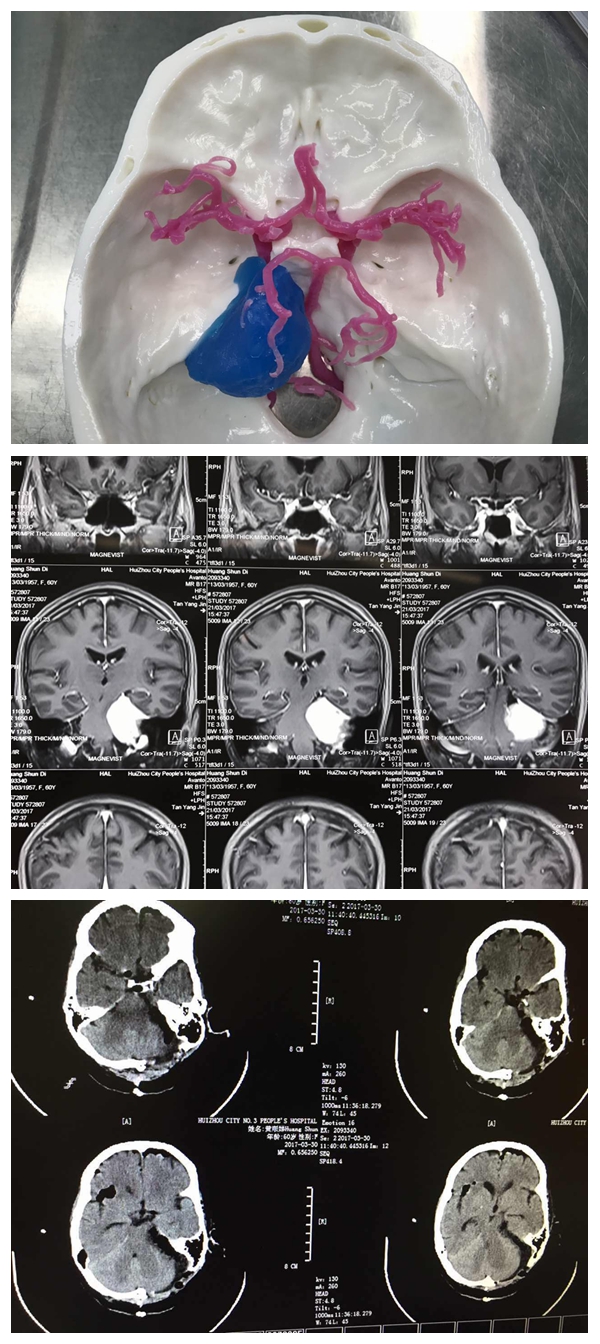

第二例3D模型

第二例為蝶骨嵴內(nèi)側(cè)及海綿竇旁腫瘤切除術(shù),腫瘤包裹了顱內(nèi)重要結(jié)構(gòu)(頸內(nèi)動(dòng)脈及其分支,視神經(jīng)),由于位置深,與重要結(jié)構(gòu)相鄰,腫瘤血供極其豐富,手術(shù)難度大。然而經(jīng)過(guò)3D模型下精準(zhǔn)的定位,以及術(shù)前充分的準(zhǔn)備及討論,手術(shù)順利完成,患者恢復(fù)良好,近期將出院。